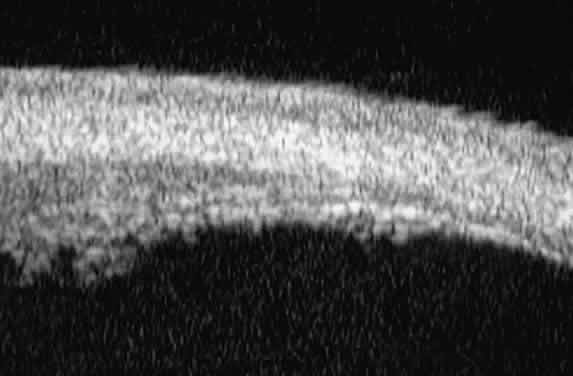

Postoperative UBM imaging of the anatomic changes caused by glaucoma surgery often helps to explain mechanisms of success and failure of the various surgical procedures (Fig. 12).3,4 After laser iridotomy, UBM can show whether the iridotomy is partial thickness (see Fig. 12A) or full thickness (see Fig. 12B) and whether the plane of curvature of the peripheral iris has changed compared with the pretreatment findings. After trabeculectomy (see Fig. 12C), UBM can show whether the scleral aperture is patent or blocked internally, whether the peripheral iridectomy is open or blocked, and whether the filtering bleb is flat, shallow, or deep.9 After tube shunt surgery (see Fig. 12D), UBM can show the position of the tip of the tube and whether its orifice is open or plugged.

Fig. 12. UBM features in glaucomatous eyes after treatment or filtering surgery. A. Incomplete peripheral iridectomy created by laser. B. Full-thickness peripheral iridectomy created by laser. C. Postoperative features of trabeculectomy including peripheral iridectomy, inner scleral defect, thin residual scleral flap, and overlying conjunctival filtering bleb. D. Tube shunt projecting radially into anterior chamber; note that the tube “shadows” deeper structures.

After any type of glaucoma filtering surgery,10 UBM can be used to detect and evaluate the extent of postoperative complications such as ciliochoroidal effusion and cyclodialysis.3,4 In ciliochoroidal effusion (Fig. 13A), UBM shows the ciliary body to be edematous and separated from the sclera by a sonolucent collection of supraciliary fluid. Many ciliochoroidal effusions that are too limited in extent to be detectable by indirect ophthalmoscopy and slit lamp biomicroscopy can be imaged by UBM. In cyclodialysis (see Fig. 13B), UBM shows a well-defined separation between the uveal tissue and the sclera in the region of the scleral spur. The width of the cleft is usually assessed best by means of limbus-concentric images through the region of interest.

Fig. 13. Complications of intraocular surgery. A. Postoperative ciliochoroidal effusion appears as slitlike spaces filled with serous fluid posterior to scleral spur. B. Postoperative cyclodialysis appears as complete separation of iris and ciliary body from sclera in region of scleral spur.